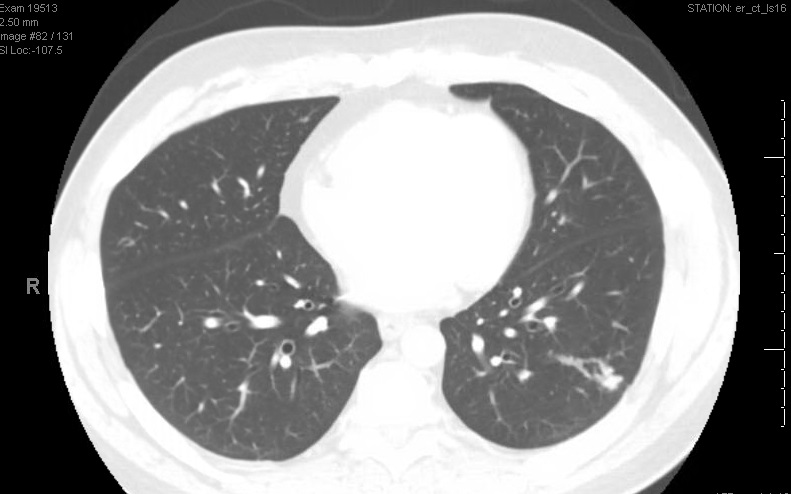

CT scan of the chest was peformed with the image below: